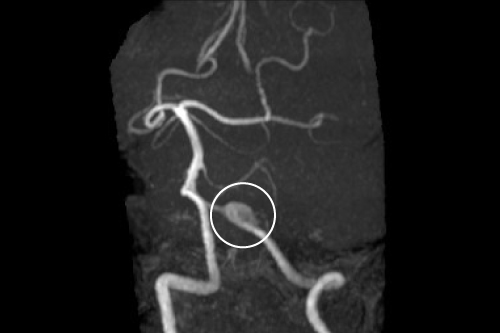

くも膜下出血

くも膜下出血の多くは脳動脈瘤が破裂することで発症します。くも膜下出血の頭痛は「人生最悪」の「突然の激しい頭痛」が特徴とされています。頭痛外来を歩いて受診するくも膜下出血(Walk in SAH)は、再破裂を予防するために、早期に発見し治療することが重要です。様子見ることなく、即日対応いたします。